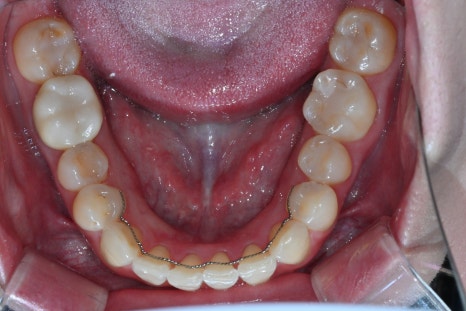

- Shaping and scanning 4 abutments for OBZERO Pure laminate

Within the possible range, the amount of reduction was minimized,

and the exact form was captured with an intraoral scanner.

- Designing 2 anterior crowns and taking impressions

The central axis of the front teeth and the bite height were accurately established.

- Checking function, speech, and esthetics after placing temporary teeth

We carefully checked the patient’s speaking habits,

the smile line, and air leakage during speech.